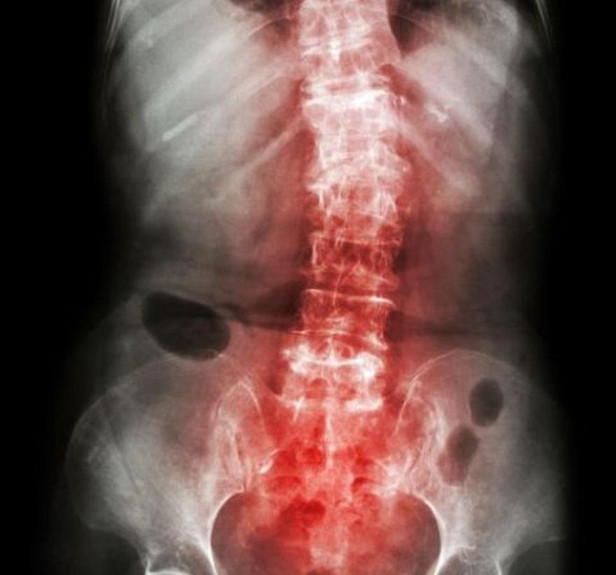

π Diagnosis & Assessment: A thorough evaluation using X-rays, MRIs, and clinical tests to determine the severity.Β